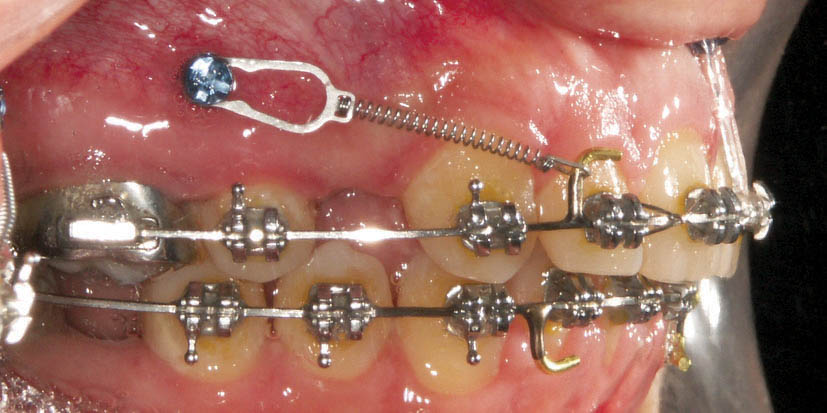

بعد از بیحسی لثه ناحیه مولر بالا که با ژلها انجام میگیرد در ناحیه مولری بین دندان 5 و 6 بالا در مرز لثه چسبنده با موکوزا با زاویه 90 درجه وارد لثه میکنیم. البته بهتر است زاویه پیچ به نحوی باشد که کمی به سمت ژنژیوال پیچ گردد. بیمار احساس فشار را دارد ولی درد ندارد (شکل 220-1). برای نواحی کام (شکل 221-1)، زیر خار قدامی بینی (شکل 222-1)، قدام بالا (شکل 223-1) و خلف پایین بهتر است از بیحسی به میزان بسیار کم استفاده کنید. البته برای خارج کردن آن اصلاً نیازی به بیحسی ندارید.

شکل 220-1: رایجترین محل برای نصب مینی اسکرو، بین دندان 5 و 6 برای افزایش انکوریج در بعد افقی است.

در زمانی که بخواهیم بعد از کشیدن پرمولرها سگمنت خلفی اصلاً جلو نیاید از مینی اسکرو استفاده میکنیم. در حالت معمولی وقتی دندان پرمولر کشیده میشود و سگمنت قدام را عقب میدهیم به صورت متقابل سگمنت خلفی هم جلو میآید. هر چه ارتفاع عمودی صورت بیشتر باشد حرکت مزیالی مولرها هم بیشتر خواهد شد. در مواقعی حرکت مزیالی مولرها خوب است (به فصل طرح درمان مراجعه نمایید) ولی در بعضی از بیماران حرکت مزیالی مولرها صحیح نیست (مانند بیماری که یک کاسپ کامل کلاسII است (شکل 220-1) و نیمرخ برجستهای دارد و قوس پائین غیرکشیدنی است، اگر پرمولرهای بالا کشیده شود باید از حرکت مزیالی مولرها جلوگیری نمود). در این مواقع فقط سگمنت قدامی باید عقب برود و فضا را ببندد. طبیعی است که بستن فضا در این بیماران اثر زیادی روی نیمرخ صورتی بیمار خواهد گذاشت (شکل 224-1 و 225-1).